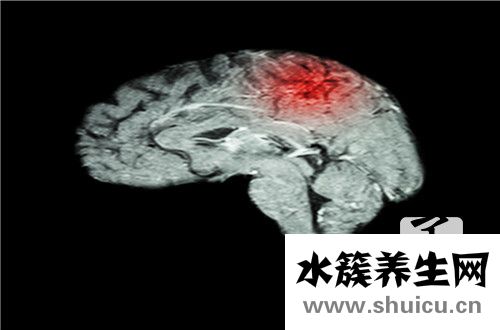

脑外科手术是一种危险的重大外科手术治疗。 手术前必须做一些准备工作以清除脑积水。 通常,使用一些药物或引流方法清除脑积水,两周后即可清除。 更严重的患者大概需要二十天。 手术后,要注意患者的...